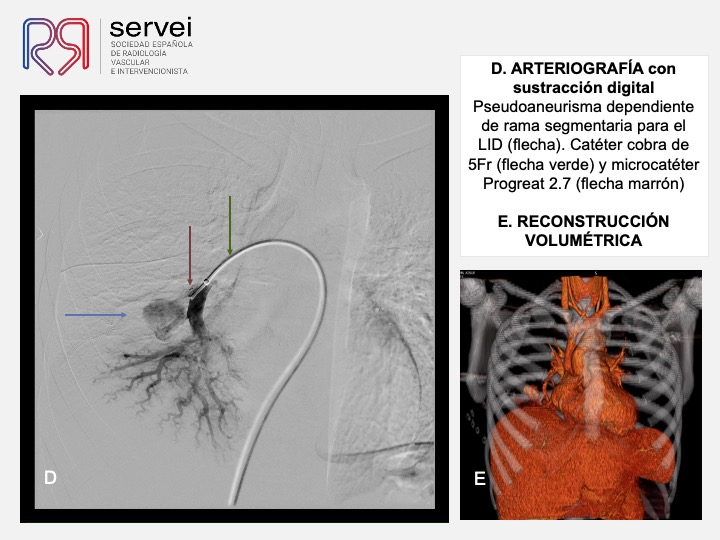

- Pseudoaneurisma pulnonar herida arma fuego 01

- Pseudoaneurisma pulnonar herida arma fuego 02

- Pseudoaneurisma pulnonar herida arma fuego 03

- Pseudoaneurisma pulnonar herida arma fuego 04

- Pseudoaneurisma pulnonar herida arma fuego 05

- Pseudoaneurisma pulnonar herida arma fuego 06

- Pseudoaneurisma pulnonar herida arma fuego 07

- Pseudoaneurisma pulnonar herida arma fuego 08

- Pseudoaneurisma pulnonar herida arma fuego 09

- Pseudoaneurisma pulnonar herida arma fuego 10

- Pseudoaneurisma pulnonar herida arma fuego 11

- Pseudoaneurisma pulnonar herida arma fuego 12